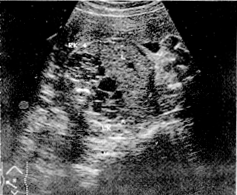

(6)B超顯示雙腎有為數眾多之暗區。